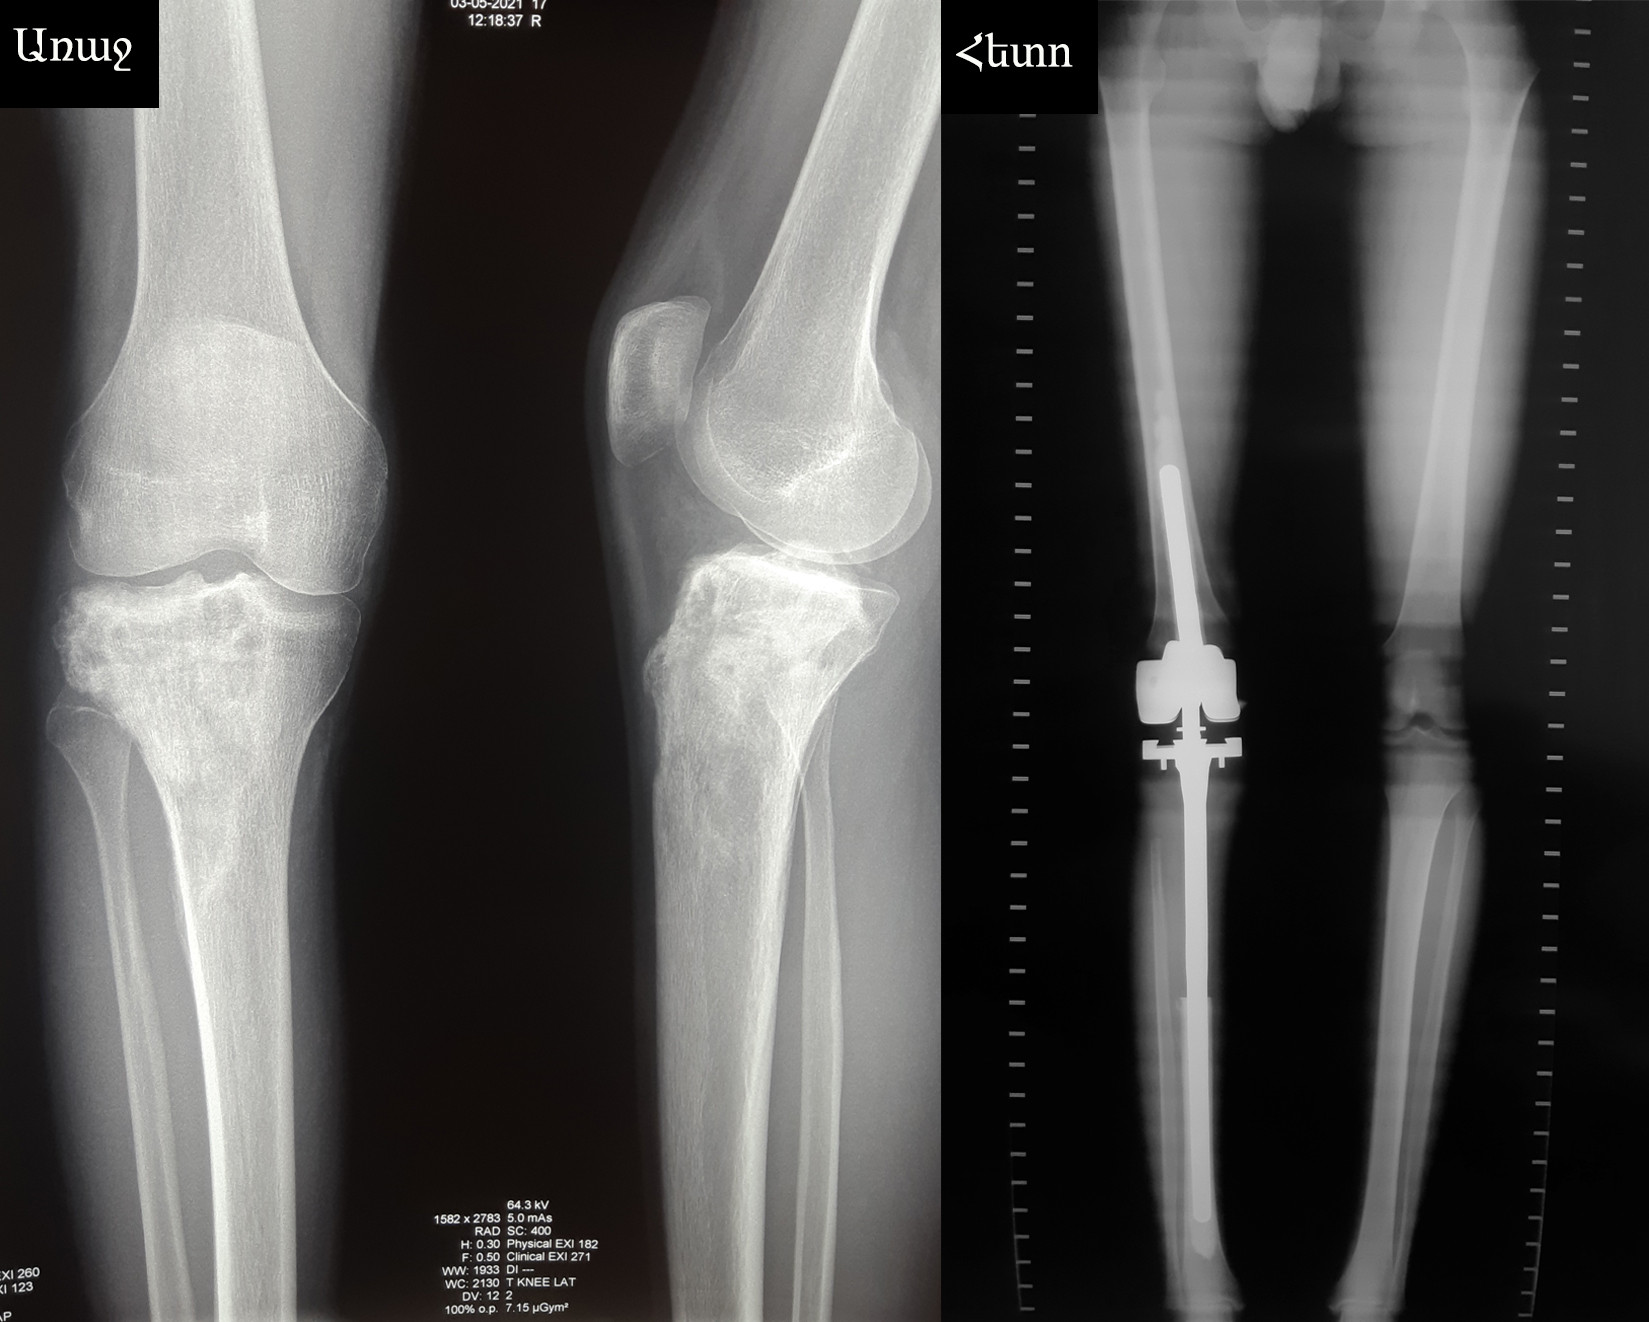

Պացիենտը 17 տարեկան է:

Ախտորոշումը՝ աջ ոլոքի վերին երրորդականի օստեոսարկոմա:

Ստացել է նախավիրահատական հինգ կուրս քիմիաթերապիա Յոյլանի անվ. Արյունաբանական կենտրոնում, որից հետո ընդունվել է «Նաիրի» բժշկական կենտրոն վիրահատական բուժման նպատակով:

Կատարվել է ոլոքի վերին երրորդականի և ծնկահոդի մասնահատում՝ ուռուցքի հեռացումով:

Առաջացած ոսկրահոդային դեֆեկտի անհատական էնդոպրոթեզավորում է կատարվել: